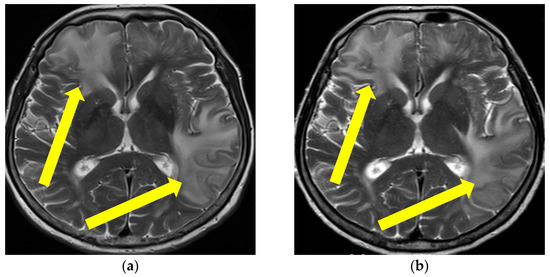

Figure 1.

Initial brain MR T2 sequence at admission and before therapy initiation (a) and one month after therapy initiation (b). Yellow arrows are showing confluent and extensive bilateral periventricular hyperintensities in (a) and reduction of hyperintensities of the same locations on (b). (Patient No. 1).

Figure 2.

Initial brain MR T2 FLAIR sequence (a), and control brain MR examination after immunosuppressive therapy initiation (b). Yellow arrows showing the locations of hyperintensities and clear regression of lesions (Patient No. 1).

Since the patient fulfilled all the criteria for the diagnosis of probable CAA-ri (age > 40 years, decreased consciousness, with the presence of behavioral changes and focal neurologic deficit, MR signs of asymmetric WMH lesions and cerebral microbleeds, with the absence of other possible causes), the patient was initially treated with antihypertensive and anti-edematous therapy, together with IV dexamethasone (8 mg/daily) for 10 days, followed by pulse methylprednisolone therapy (1000 mg/day) for 5 days, after which oral prednisone (1 mg/kg) was slowly tapered down. The patient’s neurological status improved and he showed very discrete hemiparesis and normal gait, and the patient was alert and oriented. A neurological examination was almost without significant impairment and sequelae. A control CSF examination was performed, where normal levels of protein and glycose were detected. A normal cell count was present, and no OCB were registered. Control brain MR showed edema reduction with less extended WMH lesions (Figure 1 and Figure 2). The post treatment neuropsychological examination was without significant impairment.